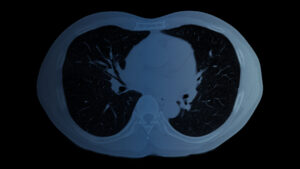

What you need to know Chest CT Scan

A Chest CT scan is a vital imaging test that creates highly detailed pictures of...